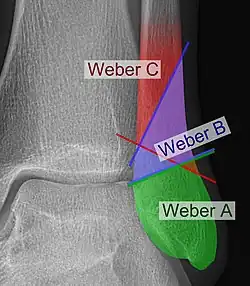

Danis–Weber classification

The Danis–Weber classification (often known just as the Weber classification) is a method of describing ankle fractures. It has three categories:[1]

Fracture of the fibula distal to the syndesmosis (the connection between the distal ends of the tibia and fibula). Typical features:

Fracture of the fibula at the level of the syndesmosis. Typical features:

Fracture of the fibula proximal to the syndesmosis. Typical features: